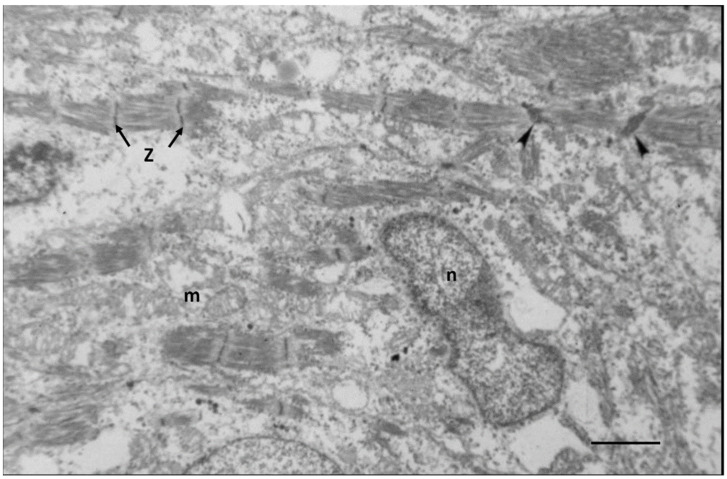

Ultrastructural studies of fetal myocardium in cell cultures [45,46], chicken embryos [47], rats [48,49], mice [50,51], and in an in vivo cell culture model of E12 rat myocardium growing in oculo [49] have identified incomplete developing structures in CMs and the endothelial and connective tissue of interstitial space. Endothelial cells forming new capillaries and interstitial connective tissue are sparse during mid-gestation, becoming more prominent near term [38,47,48,49,50,51]. Incomplete myofibrils and sarcomeres of E12 rats are loosely arranged around immature nuclei and mitochondria in spherical shaped CMs with abundant clear cytoplasmic space as shown in Figure 1.

Figure 1.

Electron micrograph of an E12 rat embryo. The nucleus (n) is immature with dispersed chromatin, mitochondria (m) are rare, endoplasmic reticulum is abundant. Myofiber fragments have immature sarcomeres bounded by Z-bands (z). Wide Z-bands (arrowheads) suggest neoformation. Bar = 2 µm.